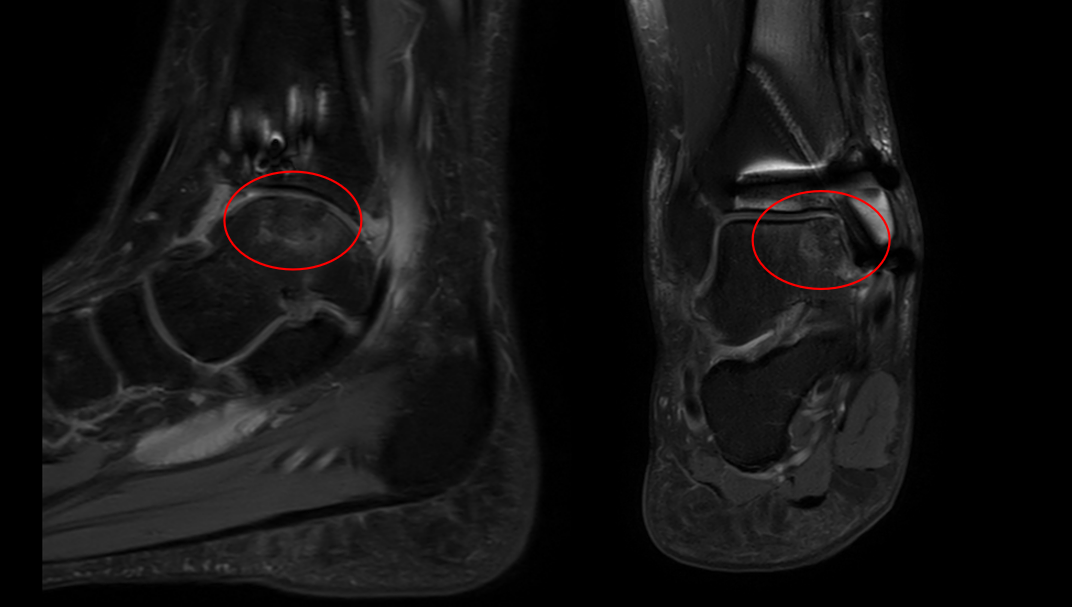

术后半年复查核磁共振,肋骨骨软骨移植物与距骨整合良好